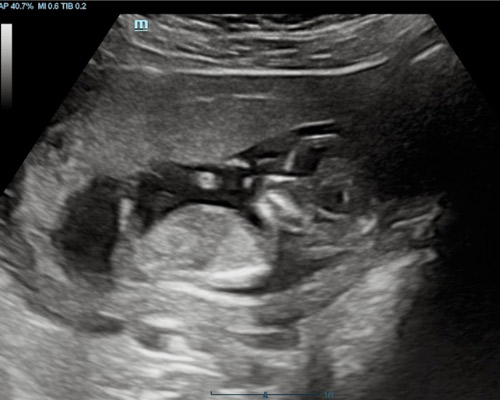

A viability scan is usually performed between 6 and 12 weeks to assess early development. It can help confirm the pregnancy, estimate dates, and check for key signs such as the gestational sac, fetal pole, and a heartbeat where visible. This scan is often chosen by those who want early clarity, have concerns, or simply wish for reassurance before their first routine appointment.

- Visual confirmation of the fetal heartbeat

- Checking for single or multiple pregnancies

The scan looks at early development, including location, measurements, and whether a heartbeat can be seen, depending on how far along you are.